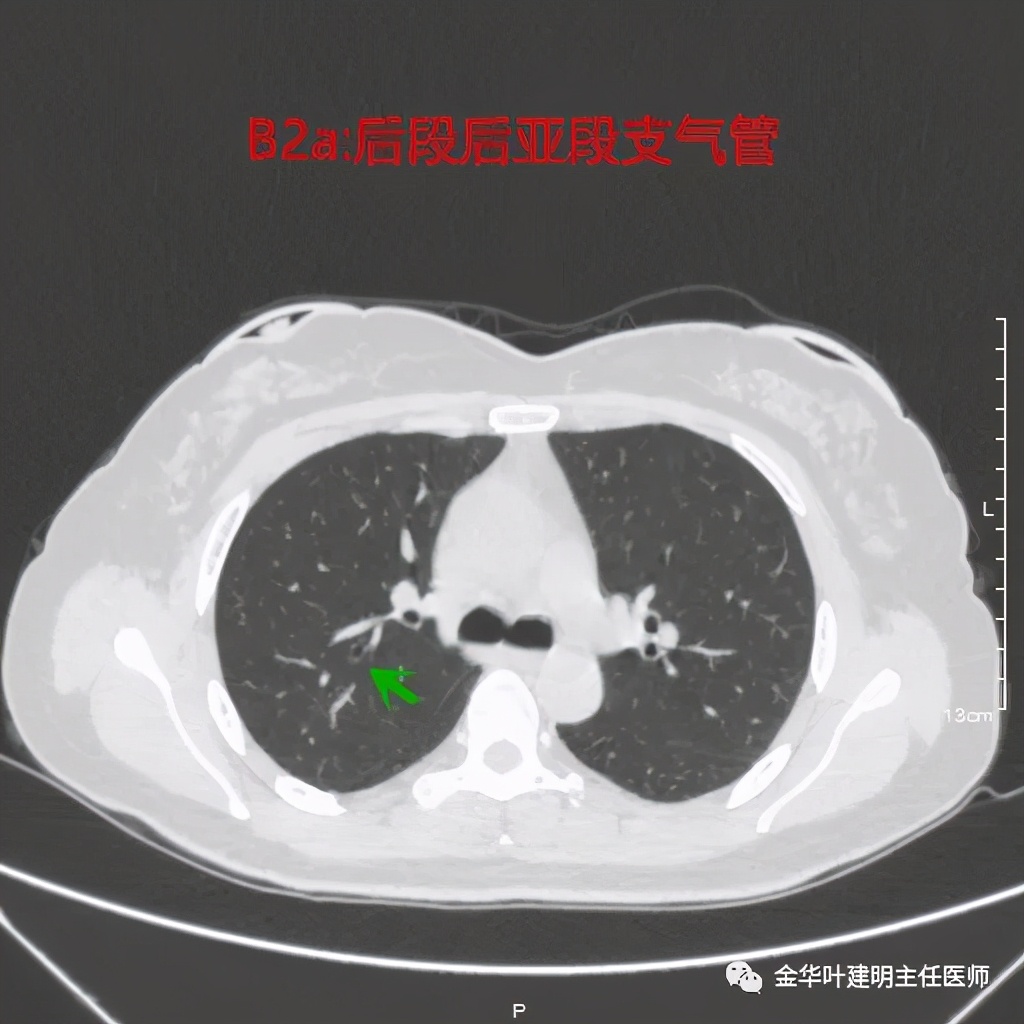

后段:同样选取最佳层面标注其亚段支气管:

这里同一层面没能见到两个亚段,绿色箭头所指这是后段后亚段支气管